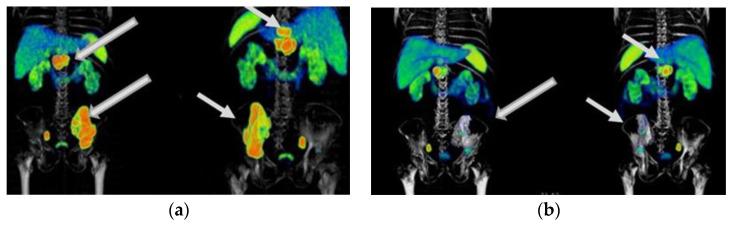

Lu-iPSMA is a novel radioligand developed at ININ-Mexico with a high affinity for the PSMA protein heavily expressed in cancer cells of approximately 95% of patients with metastatic castration-resistant prostate cancer (mCRPC). Lu-DOTATOC is a patent-free radioligand, molecularly recognized by somatostatin receptors (SSTR-2) overexpressed in cancer cells of about 80% of patients with metastatic gastroenteropancreatic neuroendocrine tumors (GEP-NET). This translational research aimed to determine the efficacy and safety of Lu-iPSMA and Lu-DOTATOC developed as GMP pharmaceutical formulations for treating progressive and advanced mCRPC and NET. One hundred and forty-five patients with mCRPC and one hundred and eighty-seven subjects with progressive NET (83% GEP-NET and 17% other NET), treated with Lu-iPSMA and Lu-DOTATOC, respectively, were evaluated. Patients received a mean dose of 7.4 GBq per administration of Lu-iPSMA (range 1-5 administrations; 394 treatment doses) or Lu-DOTATOC (range 2-8 administrations; 511 treatment doses) at intervals of 1.5-2.5 months. Efficacy was assessed by SPECT/CT or PET/CT. Results were stratified by primary tumor origin and number of doses administered. Patients with mCRPC showed overall survival (OS) of 21.7 months with decreased radiotracer tumor uptake (SUV) and PSA level in 80% and 73% of patients, respectively. In addition, a significant reduction in pain (numerical scale from 10-7 to 3-1) was observed in 88% of patients with bone metastases between one and two weeks after the second injection. In the GEP-NET population, the median progression-free survival was 34.7 months, with an OS of >44.2 months. The treatments were well tolerated. Only ten patients experienced grade ≥ 3 myelosuppression (3% of all patients). The observed safety profiles and favorable therapeutic responses demonstrated the potential of Lu-iPSMA and Lu-DOTATOC to improve overall survival and quality of life in patients with progressive and advanced mCRPC and NET.

镥-PSMA是墨西哥国立核科学研究所研发的一种新型放射性配体,对约95%的转移性去势抵抗性前列腺癌(mCRPC)患者癌细胞中高表达的PSMA蛋白具有高亲和力。镥-奥曲肽是一种无专利的放射性配体,可被约80%的转移性胃肠胰神经内分泌肿瘤(GEP-NET)患者癌细胞中过表达的生长抑素受体(SSTR-2)分子识别。这项转化研究旨在确定作为药品生产质量管理规范(GMP)制剂开发的镥-PSMA和镥-奥曲肽治疗进展期和晚期mCRPC及神经内分泌肿瘤(NET)的疗效和安全性。分别对145例mCRPC患者和187例进展期NET患者(83%为GEP-NET,17%为其他NET)进行了评估,这些患者分别接受了镥-PSMA和镥-奥曲肽治疗。患者接受镥-PSMA(范围为1至5次给药;394个治疗剂量)或镥-奥曲肽(范围为2至8次给药;511个治疗剂量),每次给药平均剂量为7.4GBq,给药间隔为1.5至2.5个月。通过单光子发射计算机断层扫描/计算机断层扫描(SPECT/CT)或正电子发射断层扫描/计算机断层扫描(PET/CT)评估疗效。结果按原发肿瘤来源和给药剂量数进行分层。mCRPC患者的总生存期(OS)为21.7个月,分别有80%和73%的患者放射性示踪剂肿瘤摄取(SUV)和前列腺特异抗原(PSA)水平降低。此外,在第二次注射后1至2周内,88%的骨转移患者疼痛显著减轻(数字评分从10 - 7降至3 - 1)。在GEP-NET人群中,无进展生存期的中位数为34.7个月,总生存期>44.2个月。这些治疗耐受性良好。只有10例患者出现≥3级骨髓抑制(占所有患者的3%)。观察到的安全性概况和良好的治疗反应表明,镥-PSMA和镥-奥曲肽有潜力改善进展期和晚期mCRPC及NET患者的总生存期和生活质量。